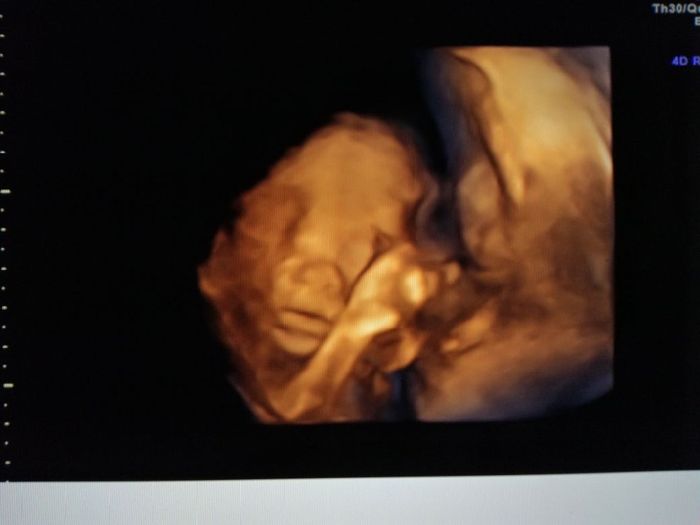

Ciao ragazze, in un attacco di insonnia vi posto le foto della morfologica in 4d di ieri๐Ÿ˜! La polpetta sta alla grande, pesa 430 gr ed รจ tale e quale al papa!๐Ÿ˜‚๐Ÿ˜‚๐Ÿ˜‚tutti questi mesi nella pancia con noi mamme, e poi sono la fotocopia dei mariti!!!๐Ÿ˜‚๐Ÿ˜‚๐Ÿ˜‚un bacio da me e e Bianca 21+5๐Ÿ’–notte!!!!

Morfologica, che spettacolo!!!! - 3